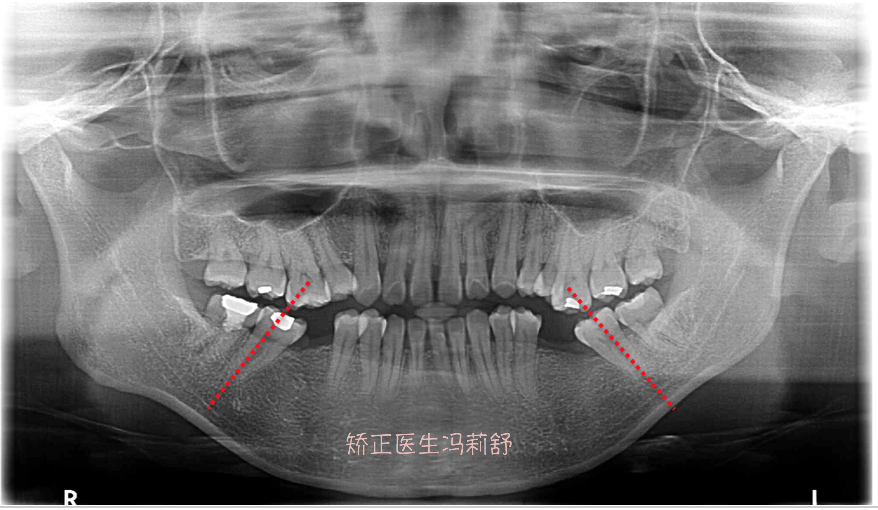

- 相邻的健康好牙会失去支撑,向缺牙空隙倾斜,移位,松动,相邻牙齿也

- 6,牙齿倾斜或牙齿长期缺损,导致相邻牙齿移位.

- 缺牙空隙内倾斜,移位,缺牙空隙相对应的牙齿将因无力量而逐渐伸长

- (会导致响铃牙齿倾斜或对咬牙增长)

- 缺失牙临近的牙齿向缺隙处倾斜

- 缺牙空隙内倾斜,移位,缺牙空隙相对应的牙齿将因无力量而逐渐伸长